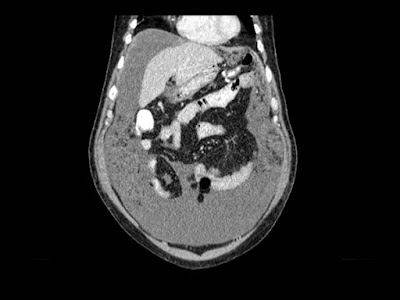

Mujer de 57 años.

Cuadro clínico de 1 mes de evolución caracterizado por distensión abdominal e hiporexia.